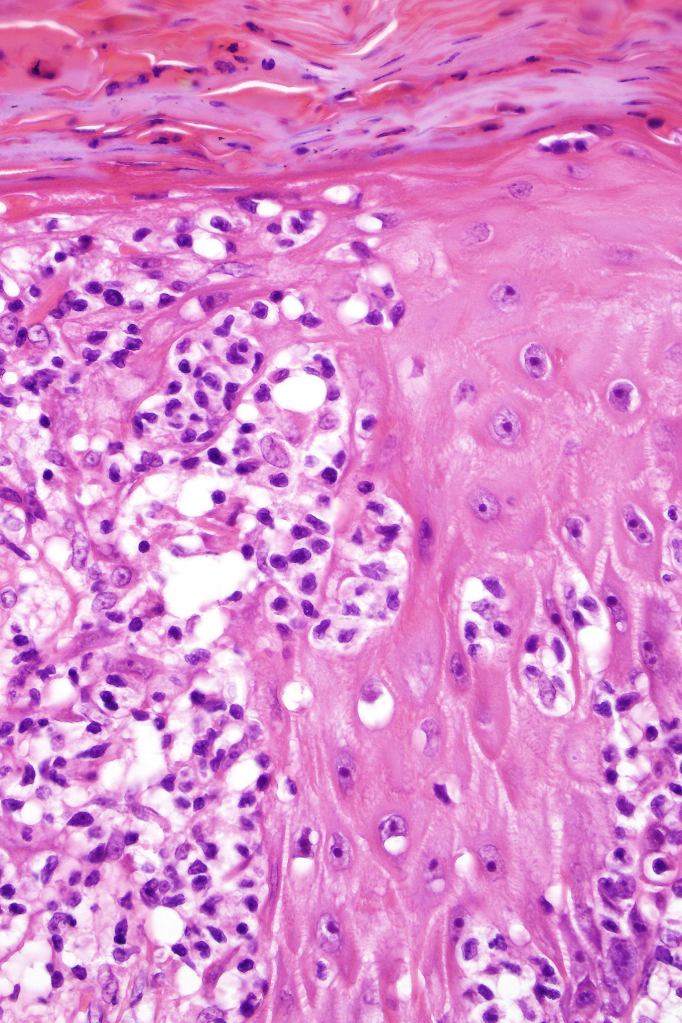

•Hyperkeratosis/parakeratosis

•Acanthosis often psoriasiform

•Very marked epidermotropic infiltrate of atypical lymphocytes including Sézary cells

•Perinuclear halo often present

•Pautrier-like microabscesses

•Superficial dermal perivascular lymphohistiocytic infiltrate with only sparse or absent atypical forms